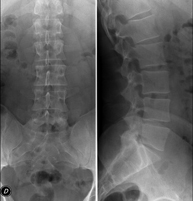

Técnica mediante la cual, utilizando rayos X, se obtienen imágenes de la columna dorsal para su estudio. Indicaciones: traumatismo, dolor de espalda. - RX Columna lumbar

Técnica mediante la cual, utilizando rayos X, se obtienen imágenes de la columna lumbar para su estudio. Indicaciones: ciática, traumatismo, dolor lumbar. - RX Sacro-cóccix

Técnica mediante la cual, utilizando rayos X, se obtienen imágenes de toda la columna vertebral para su estudio, valorando especialmente la presencia de escoliosis y dismetrías pélvicas.